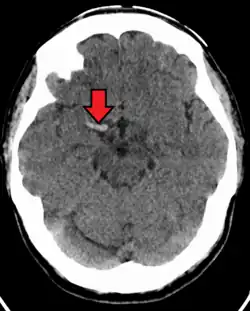

Stroke

Acute thrombus in the right MCA M1 branch

A stroke is the rapid decline of brain function due to a disturbance in the supply of blood to the brain.[6] This can be due to ischemia, thrombus, embolus (a lodged particle) or hemorrhage (a bleed).[6]

In thrombotic stroke, a thrombus (blood clot) usually forms around atherosclerotic plaques. Since blockage of the artery is gradual, the onset of symptomatic thrombotic strokes is slower. Thrombotic stroke can be divided into two categories — large vessel disease or small vessel disease. The former affects vessels such as the internal carotids, vertebral and the circle of Willis. The latter can affect smaller vessels, such as the branches of the circle of Willis.